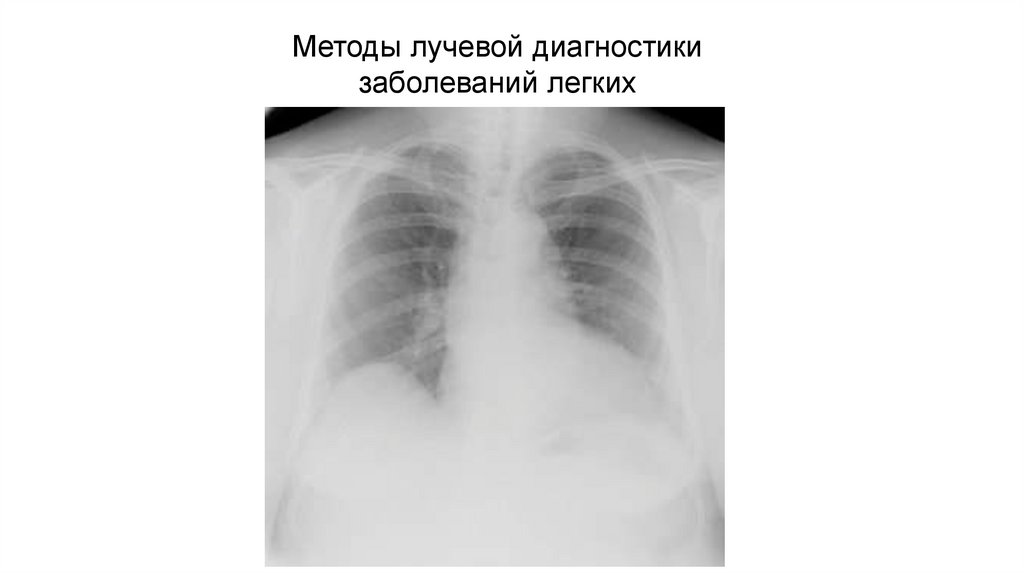

Нормальная конфигурация сердца (нормостеническая)